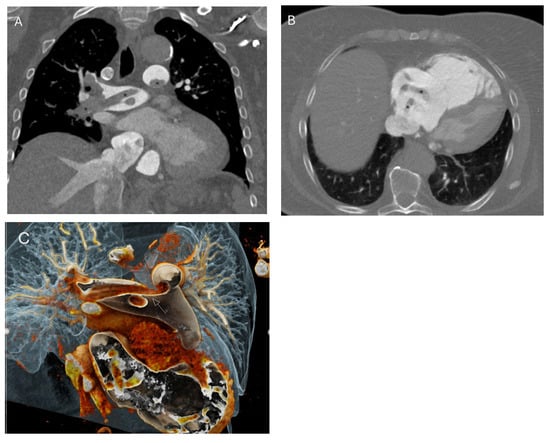

图1. 计算机断层肺血管造影(Computed Tomography Pulmonary Angiography, CTPA)显示左右肺动脉、叶间动脉以及大部分段支存在造影剂填充缺损(用星号*标注),这与大面积肺栓塞(

A)一致;同时右心房内也发现一个蛇形填充缺损(

B),符合移动性血栓(CIT)的特征。体积重建图像(

C)显示主肺动脉和右心室内有蛇形血栓。移动性血栓通常起源于深部盆腔静脉,可随时进入肺循环,属于医疗紧急情况[

1]。因此,早期诊断至关重要,尤其是在血流动力学不稳定的患者中。该患者为70岁女性,有近期腹部手术史,表现为急性呼吸困难和阻塞性休克,血压为59/29毫米汞柱,脉搏90次/分钟,氧饱和度(SpO

2)为98%,右心扩大,提示右心负荷过重。